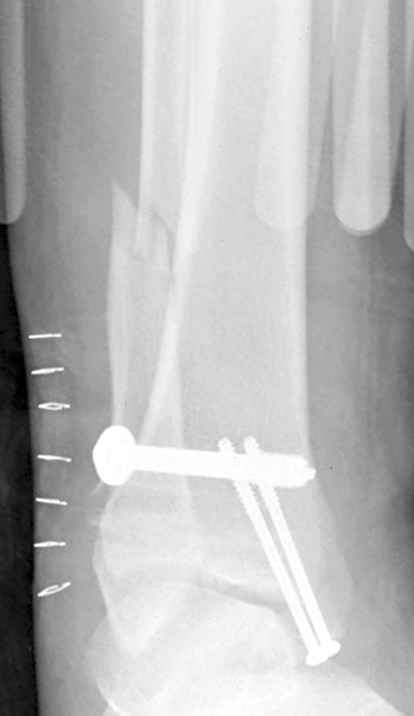

Недавний случай, больной 56 лет получил политравму в Англии, после переведен в США, где его успешно лечил местный ортопед, огромная статья в газете об успешной операции, своеобразный пиар, из-за того, что больной был американский пожарник на пенсии, и за его переезд было заплачено международным пожарным союзом, короче по другим показаниям перевели больного в наш университетский госпиталь.

После 5-6 недели после травмы сделана повторная операция, обошлись без удлинения малоберцовой.